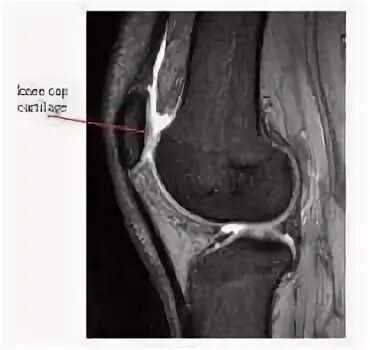

Повреждение хряща по outerbridge